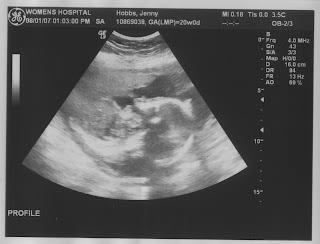

I had my ultrasound today and the technician wasn't sure of the gender of our baby but she decided that it's probably a boy... here are some pictures of our cute little Mario.

We are so happy and excited about our little Mario.

Mouth closed